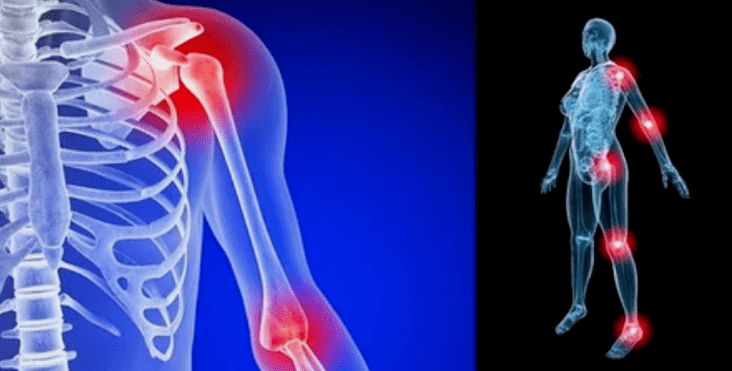

The manifestations of the disease vary slightly depending on the localization, most often the signs are reflected in the knees, shoulders and hip joints, due to the high load.

- Pain they have low severity in the initial phase, with the worsening of the sensation state intensified.Initially, the joints were injured only after they wake up, after a slight warm heat, the sensations disappear.Over time, the pains appear at night, they are very worried during and after prolonged walking, jogging, etc.In the final stage, pain syndrome follows a person all the time;

- limited amplitude of movements.The stiffness of actions indicates anatomical changes in the structure.At first it manifests in the morning, then the daily movements are limited.In order not to provoke the deterioration of the condition, the work must be varied and easy, otherwise the patient will not be able to unlock and squeeze the limb over time.Over time, there is a risk of contracting, from which a person loses motor ability;

- Crowns during movements - belongs to nonspecific manifestations of arthrosis.The disease is characterized by the emergence of crunch in a single fusion (except polyarthrosis), accompanied by discomfort, pain and limited actions.The nature of the current is similar to the wave - at first it manifests poorly, gradually intensified, but in 3 phases disappears;

- Swelling with redness.Localized localized near the diseased joint, this indicates an inflammatory process and progression of the disease.The doctor understands that synovial shells are affected, this provokes fluid accumulation and increased pain;

Deformities of the limbs.It appears in a neglected form of the disease, indicates the complete destruction of the cartilage tissue and the appearance of osteophytes.In this condition, the pressure on the joints at the top and below increases, from which bending can affect the entire limb.